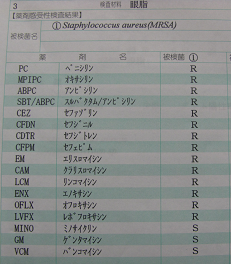

ウィルスによる風邪をこじらせると、細菌を原因とした肺炎を起こすことがあるように、ウィルス結膜炎などの目が弱っている時には、細菌が繁殖しやすいために、予防の目的で最近に対する抗生物質を処方することは多々あります。(点眼薬の抗生物質は短期の使用であれば、副作用が少ないために、予防として処方する先生が大多数のようです。)